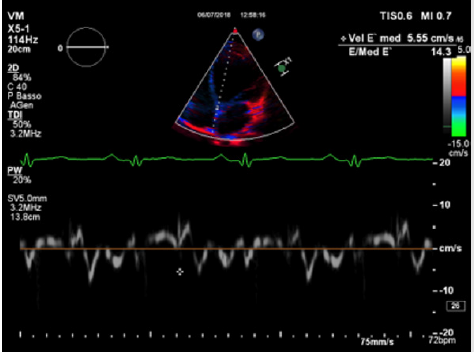

Physical examination showed a muscular man, the apex beat was not evident, the jugular at baseline showed an absent X’ descent with a positive hepato-jugular reflux and heart sounds were regular at the auscultation ; there was also minimal ankle swelling and , bilateral basal crackling rattles were audible at lung auscultation. The ECG showed a sinus rhythm with a frequency of 88 bpm, signs of left atrial enlargement, a left axial deviation and negative T-waves on D1 and aVL and from V4 to V6; no previous recent ECG was available for comparison. Chest X-ray showed pulmonary edema and an acute bronchopneumonia focus. Transthoracic echocardiography (TTE) revealed a dilated cardiomyopathy with severe left ventricular systolic dysfunction (LVEF 23% calculated with the Simpson biplane method) and dilatation (telediastolic diameter 79 mm) with moderate uniform hypertrophy (Figure 1a & 1b). There was grade II diastolic dysfunction (E/A waves ratio 1,9; E wave deceleration time 144 msec), “B-bump” on M-mode examination at the mitral valve level and an average E/e’ at tissue doppler analysis at the upper limit of the “grey zone”: 14 (Figure 2a-2d); global longitudinal peak systolic strain (GLPSS) was -7,4%; the left atrium was dilated; the right ventricle was dilated, slightly hypocontractile (tricuspidal annular plane systolic excursion, TAPSE, 16 mm) with a dilated right atrium; the inferior cava vein showed a normal dimension and collapsibility.

Figure 2c: An average E/e’ ratio at TDI analysis at basal septal and lateral level of 14 (grey zone).